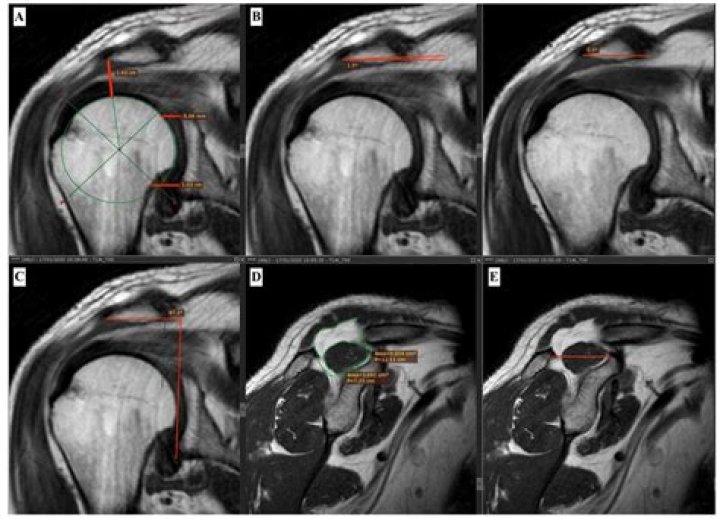

MRI gives clear views of rotator cuff tears, injuries to the biceps tendon and damage to the glenoid labrum, the soft fibrous tissue rim that helps stabilize the joint. MR imaging of the shoulder is typically performed to diagnose or evaluate: degenerative joint disorders such as arthritis and labral tears.

An MRI scan is often done to diagnose a SLAP tear and other potential injuries to the muscles, tendons, ligaments, and cartilage in the shoulder. Because of the many overlapping and interwoven structures in the shoulder, it is possible for an MRI scan to miss a smaller tear.

Results: For full thickness rotator cuff tears, MRI and arthroscopy detected them in 76 and 82 patients, respectively. One such tear found by MRI could not be confirmed by arthroscopy. MRI missed 4 subscapularis and 3 supraspinatus tears.

Do rotator cuff tears always show on MRI?